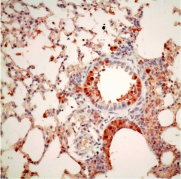

在Nature Communications發表的一項最新的研究中, 香港大學新發傳染病國家重點實驗室和香港大學李嘉誠醫學院微生物學系副教授陳鴻霖博士和微生物學系講座教授、霍英東基金教授 (傳染病學) 袁國勇教授帶領的研究團隊通過對H7N9、H5N1禽流感病毒和H3N2季節性流感病毒研究發現,不同禽流感病毒的複製酶體系的PB2亞基可能發生不同類型的適應性變異使得病毒能夠在哺乳類動物(包括人)細胞中繁殖;港大的這項研究發現H7N9禽流感病毒的複製酶體系的PB2基因有多種類型的適應性變異,這可能可以部分解釋H7N9禽流感病毒具有與其它禽流感病毒不同適應機制,使得它感染人的能力高於其它禽流感病毒。他們的研究還發現其中一種變異PB2-526在部分H7N9和印度尼西亞人感染的H5N1病毒中出現,因為以前一直沒在印度尼西亞H5N1禽流感病毒發現跟其它地區人類感染H5N1病毒相同的PB2適應性變異,港大的發現首次解釋了印度尼西亞H5N1禽流感病毒感染人類的PB2適應性變異特性。 PB2-526R變異還能夠增強其它類型的PB2變異(如PB2-627K)在哺乳類動物細胞繁殖的能力和致病性,他們的研究發現, 季節性流感H3N2在1968年形成後不久,從1970年左右在原有的PB2-627K的基礎上再獲得PB2-526R的適應性, PB2-526R和PB2-627K雙適應標記的病毒繁殖高於單獨具有PB2-627K的病毒,這也許可以部分解釋了H3N2季節性流感的傳播能力和致病性普遍高於另一種季節性流感H1N1病毒的原因。港大的這些研究發現進一步解開了禽流感病毒跨種感染和在人類細胞繁殖的必要條件,並為今後禽流感病毒監測提供了新的跨種感染、傳播和宿主適應分子標記物。